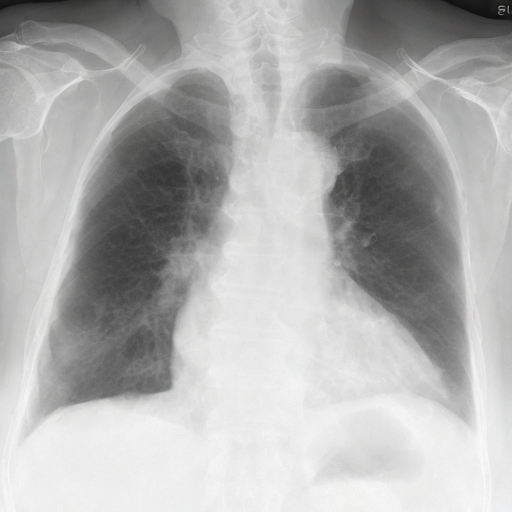

Let's load an example image of a patient with influenza.

import requests

For this example, we will remove the visual appearance of influence from the lungs, while preventing changes from happening to the rest of the image. To do this, we create a mask of the lung regions and use this as the edit_mask which defines the region we wish the editing prompt to be applied to. Since we want the rest of the image to remain unchanged, we use the inverse as the keep_mask which defines the region where edits are discouraged from taking place.